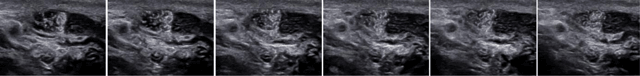

Figure 3

Selected images of an ultrasound film. Oscillating movement of the hyperehoic particles.